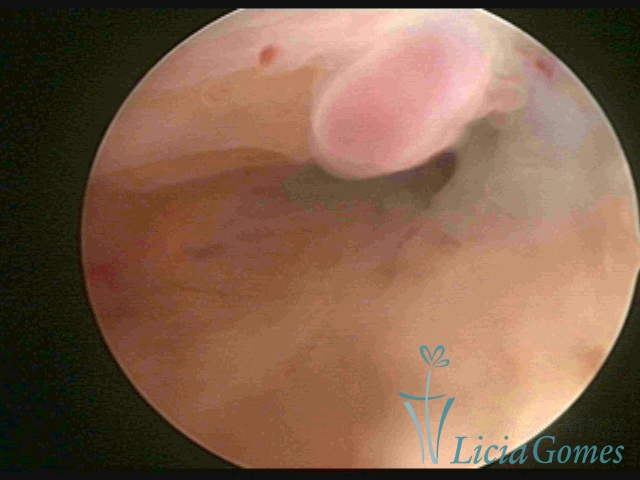

PÓLIPOS ENDOCERVICAIS

São tumores benignos, resultantes da proliferação focal reativa aos processos inflamatórios ou à situações de hiperestrogenismo, e podem ter sésseis (com a base de implantação larga) ou pediculados do epitélio.